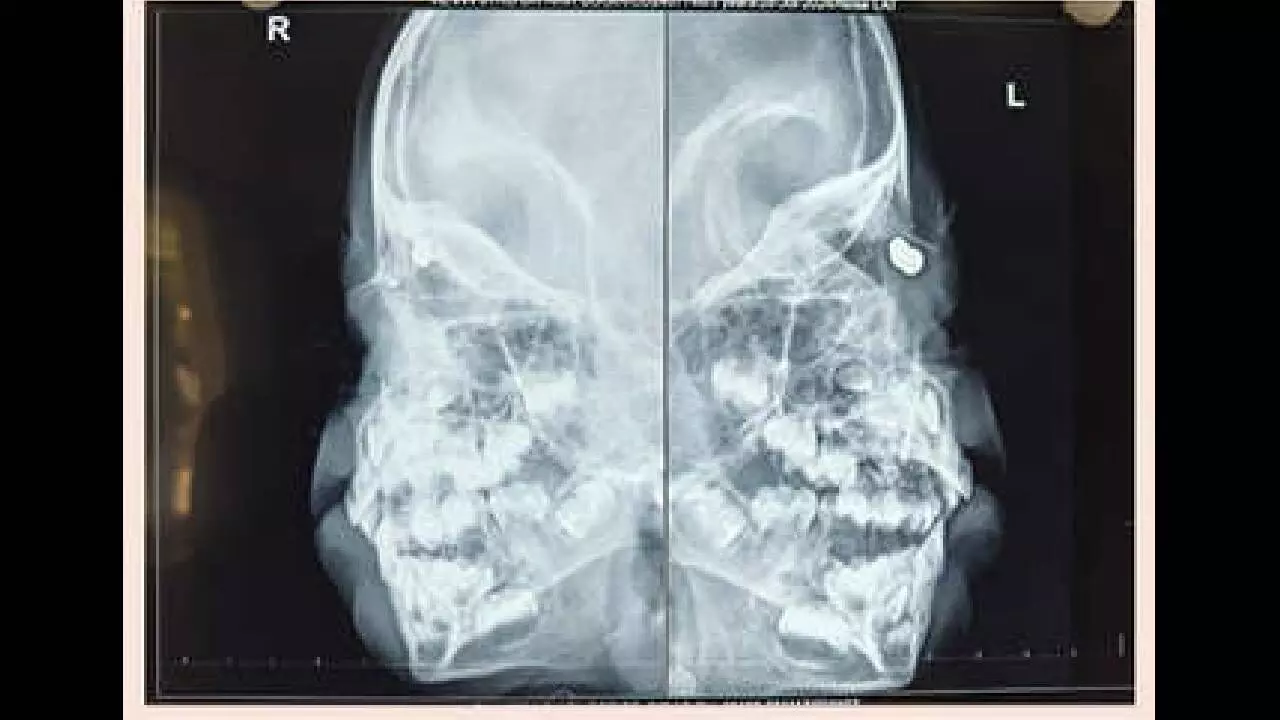

Hyderabad: Doctors at Sankara Eye Hospital, here, successfully treated a three-year-old boy who sustained a rare orbital injury after an accidental air gun pellet entered his face and migrated close to the eye. The child was referred to Sankara Eye Hospital after multiple initial consultations failed to detect the seriousness of the injury. The incident occurred while the child was playing with cousins when an air gun pellet was accidentally discharged, entering through the root of the nose. Although initial X-rays at a local hospital did not reveal the presence of the pellet and the child was discharged with conservative treatment, the parents noticed a bluish discolouration on the upper eyelid a few days later. This prompted further evaluation and referral to Sankara Eye Hospital, Hyderabad, for specialist care. Detailed examination and imaging revealed a metallic pellet measuring approximately 7–8 mm lodged extremely close to the eyeball. The child underwent a successful anterior orbitotomy with foreign body removal under general anaesthesia. The procedure was performed by Dr. Sirisha Polkampally, Consultant – Orbit & Oculoplasty and Cataract Surgeon at Sankara Eye Hospital, Hyderabad.